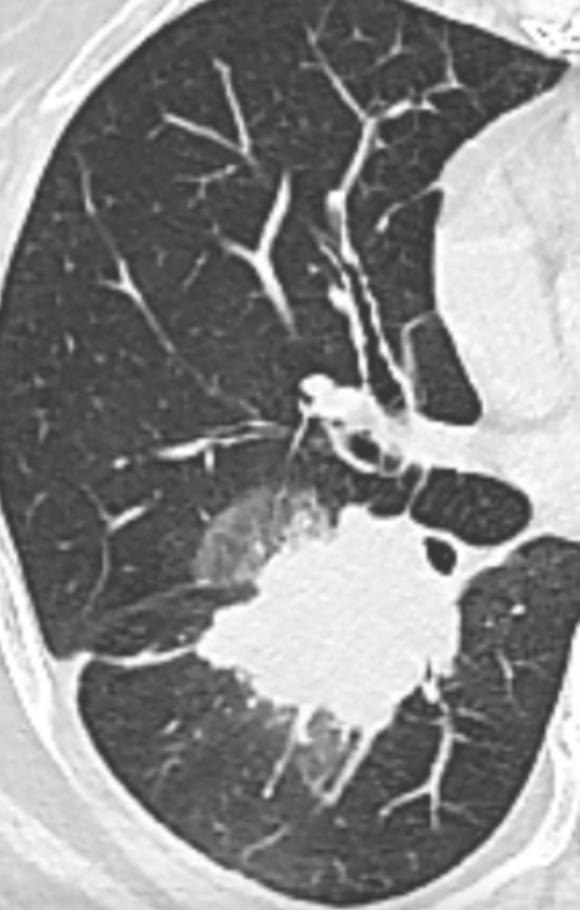

第一次看到家属咨询说当地医院确认是晚期,已经不能手术,在崩溃之余找到了一位号称学习黄帝内经的医生,吃起了一天3000的中药。我当时看到之后又震惊又心疼,仔细看了片子之后判断应该不是肺癌晚期,很可能是多原发早期肺癌,双肺的大包块很可能是混合性磨玻璃结节演变发展而成的。在我的极力劝说之下,依然没能说动这对仿佛抓住最后一根救命稻草的姐弟,放弃高价中药。遗憾之余我还是不想放弃,继续联系发帖的家属,但是没收到任何回答。

在第二城市的大医院我妈做了所有检查,又再次穿刺,确诊,基因检测。戴主任焦急万分,说我们为什么还要让病人遭受穿刺之苦?很明显地能看出来结果。可是我们不懂啊主任,对于大夫要求检查的所有项目,我们只能听之任之。检查完了,我妈妈是二期,双肺都有肿瘤,左肺2.0厘米大小,右肺最大的时候长到接近5厘米了。并且右边没有可以吃的靶向药!因为两边都有,右边长得位置又不好,长在气管边上了。他们也没有办法手术,劝我们出院了!也就是让我们认命了!这怎么可以呀?不能就这么认命,我妈妈才59岁!受了一辈子苦,遭了一辈子罪。我不甘心,又回到贴吧,想求戴主任,无论如何都要求得戴主任帮妈妈治疗!现在唯一可以救妈妈的只有戴主任了!

找到我当初发起的帖子,在回复里恳请主任原谅我们的无知和不以为然,求戴主任救救我妈妈。没想到,戴主任很快回复我们,什么怪罪的话语也没有,看完片子马上给我们加号,叫我们去重庆面诊。从2021年6月开始在戴主任和李满元主治大夫的诊治下,经过四次化疗加免疫治疗后,右肺肿瘤从最初的5.2厘米小到0.4厘米了,左肺还是2.0厘米还有一点点长。本来2021年11月份去准备右肺手术。后来戴主任说左边比较危险,先做左边的。于是妈妈在2021年11月23日把左肺的肿瘤扣掉了。左边后续不需要任何治疗。

前后历经一年,双侧大包块,虽然艰难,但成功手术就是硬道理。结节虽大,但周围有磨玻璃影,病理有贴壁成分,估计预后还不错。加油!